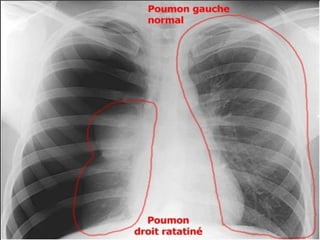

Définition du caractère complet :

 PNO complet: décollement de tout le poumon, quelle

que soit l’importance de l’épanchement.

 PNO incomplet: décollement partiel du poumon

(sommet++).

Appréciation de la taille du pneumothorax :

   mesure de la distance séparant la ligne

bordante du sommet :

< ou = 3 cm : Faible abondance.

> 3 cm : moyenne ou forte abondance.

   L’idéal : volume du pneumothorax exprimé en

%.

V = 1 – (B3/A3)*100.